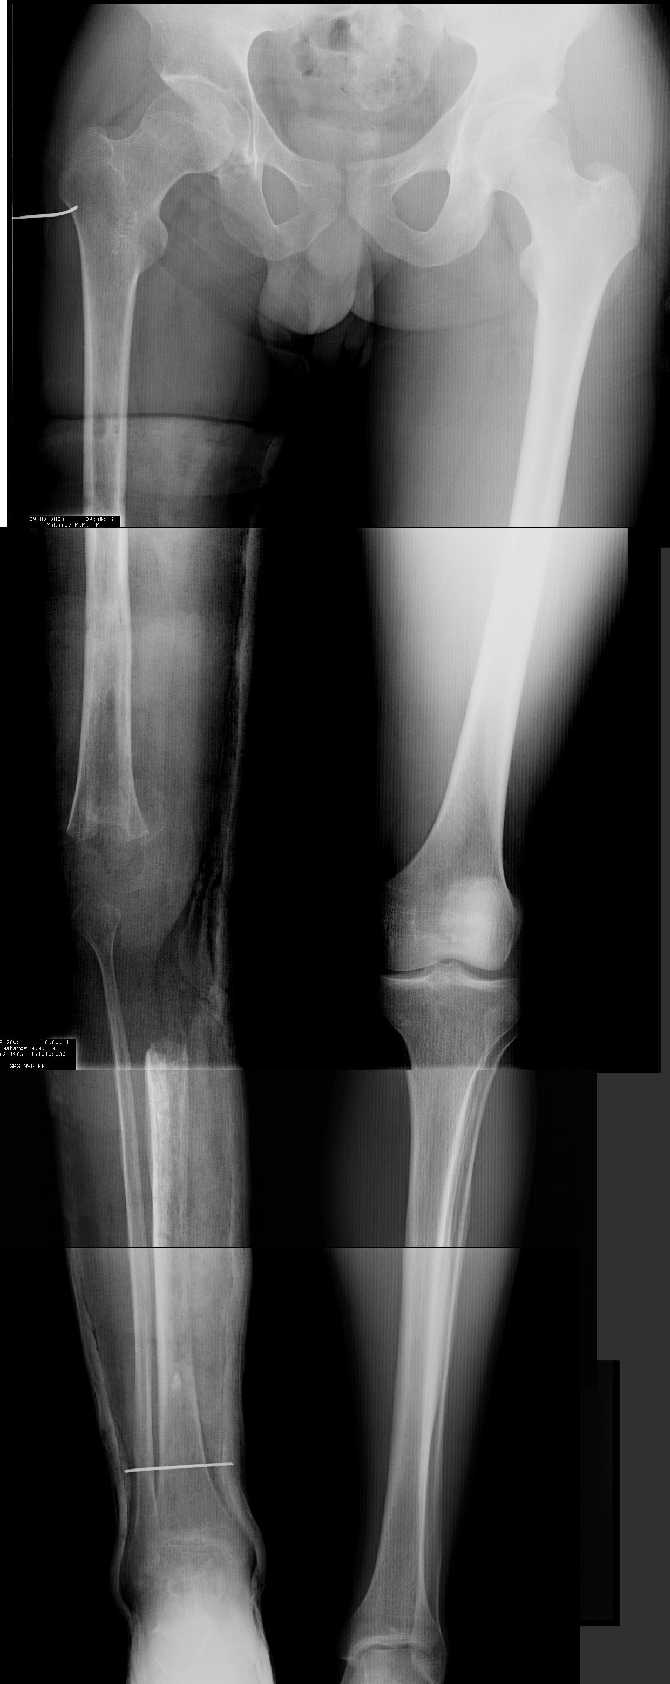

Даже по этим коротким снимкам видно, что варусная деформация на уровне бедра. Хотя для полноценной оценки оси сделать надо снимок всей конечности, от таза до стопы. Наклеить метки на кожу, по которым сделать склейку. И профиль бы тоже неплохо посмотреть.

Уважаемый Антон, при определении уровня остеотомии и величины коррекции руководствуемся, обычно, необходимостью обеспечить нормаль механической оси к середине опорной поверхности большеберцовой кости. Расчет производится по рентгенограмме (рентгенограммам) конечности под нагрузкой, которые визуализируют положение головки бедренной кости относительно таранной кости. На представленных рентгенограммах определить эти реперные точки (и заслужить Вашу зараннюю благодарность) не представляется возможным. Остается неясным с каким исходом сросся перелом правой большеберцовой кости. Складывается впечатление, что нанесены не механические, а анатомические оси. Исправлять проще за счет "минус - кость", но механически правильнее "плюс". Чтобы выполнить механические требования, иногда на ряду с угловой коррекцией (деваризация-экстензия, т.к. имеется не только разгибательная, но и сгибательная контрактура)необходимо медиолатеральное смещение.

Прежде всего необходимо выполнить рентгенографию в таком положении, как это показано на рис.

После этого представится возможность оценить ось и сравнитьеё с нормой Рисунки из кники Dror Paley - Принципы коррекции деформаций. Этой теме посвящены 800 страниц. Хотя, учитывая контрактуру, это исследование не будет исчерпывающим.

имеется S-образная деформация бедра на фоне "многооскольчатого

перелома правой бедреннойљ кости на границе средней и нижней трети со смещением"

(хотя "длинные" снимки конечно же не помешали бы...)

Почему же не вмешаться на в/3 голени (вальгизировать)?

По крайней мере это не усугубит контрактуры в коленном суставе но

позволит нормально перераспределить нагрузку...